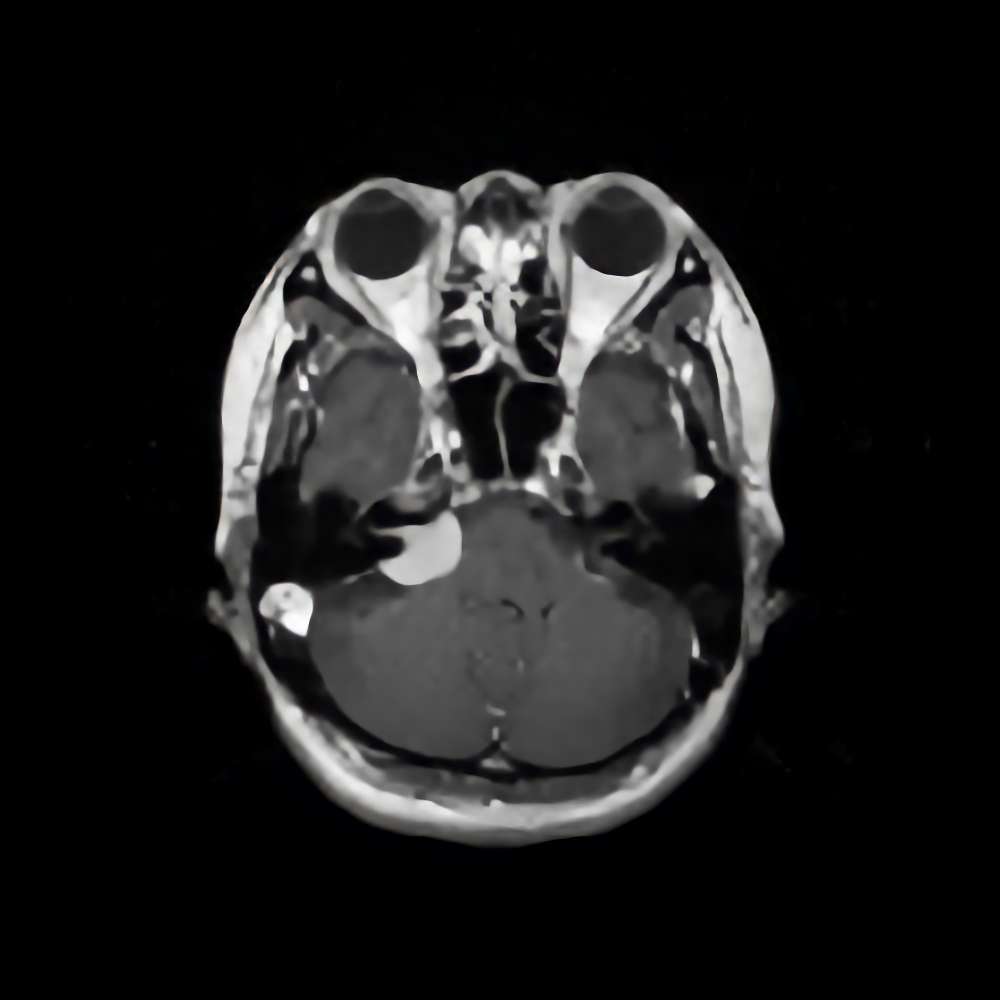

側頭葉膠芽腫

No.’16_129 手術前1

No.’16_129 摘出 前

No.’16_129 摘出 後